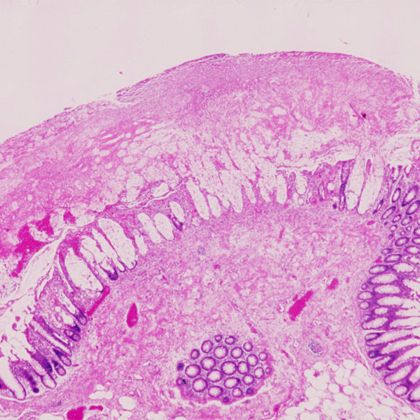

- Toksyny A i B – jak działają na jelita: Toksyny A i B wydzielane przez bakterię C. difficile działają uszkadzająco na błonę śluzową jelit, co prowadzi do zwiększonej przepuszczalności bariery jelitowej, stanu zapalnego oraz zaburzeń funkcjonowania jelit.

- Kolonoskopia i sigmoidoskopia: Kolonoskopia i sigmoidoskopia mogą być wykonywane w celu oceny stanu błony śluzowej jelit oraz ewentualnego wykluczenia innych schorzeń jelitowych, które mogą przypominać objawy RZI.